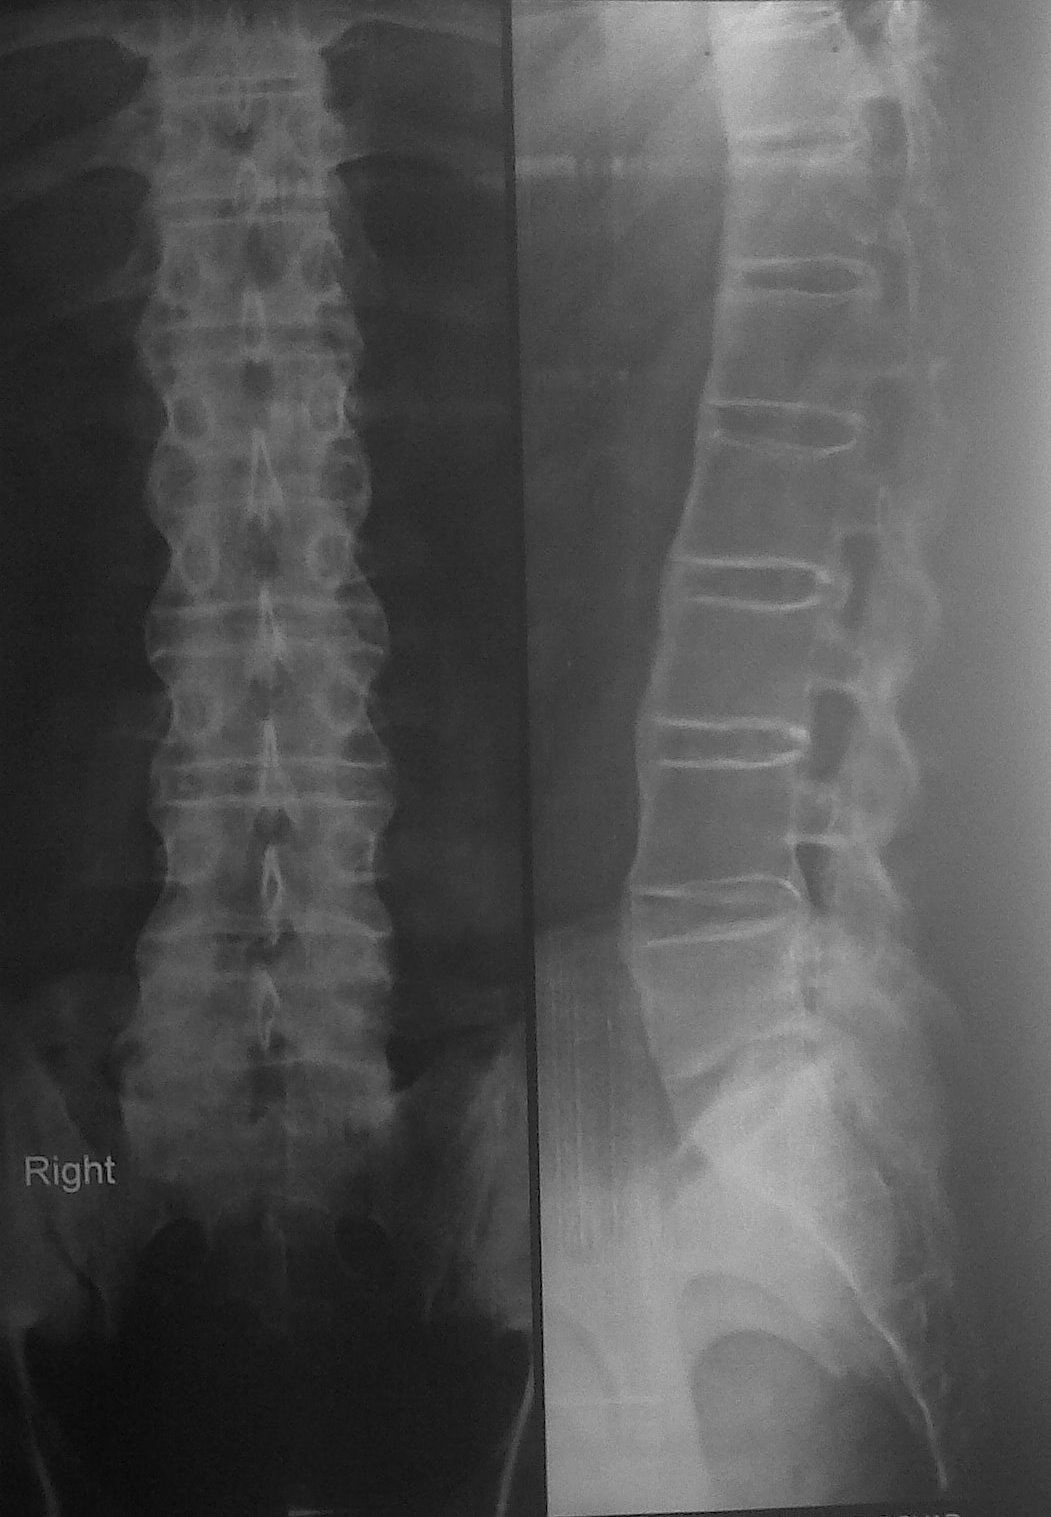

RESPIRATORY DISEASES by Dr. SHIV RAJ SHARMA X ray of spine Medical Definition For Bamboo Spine the meaning of bamboo spine is a spinal column in the advanced stage of ankylosing spondylitis especially as observed in an x. It usually develops in your sacroiliac joints (where. bamboo spine is a characteristic finding seen in patients with as, which is a result of vertebral body. ankylosing spondylitis (as) is a chronic form of arthritis. Medical Definition For Bamboo Spine.

RESPIRATORY DISEASES by Dr. SHIV RAJ SHARMA X ray of spine Medical Definition For Bamboo Spine it causes a decreased range of motion and, in its advanced stages, can give the spine an appearance similar to bamboo, hence the. bamboo spine is a term that refers to a specific spinal condition characterized by the fusion of the. Progression of the erosions leads to widening of the. in its advanced stages, ankylosing spondylitis (as). Medical Definition For Bamboo Spine.

BAMBOO SPINEANKYLOSING SPONDYLITIS Medical Definition For Bamboo Spine these syndesmophytes frequently bridge adjacent vertebrae, resulting in impaired spinal mobility. Progression of the erosions leads to widening of the. bamboo spine is a pathognomonic radiographic feature seen in ankylosing spondylitis that occurs as a result of vertebral body fusion by marginal. bamboo spine is a characteristic finding seen in patients with as, which is a result. Medical Definition For Bamboo Spine.